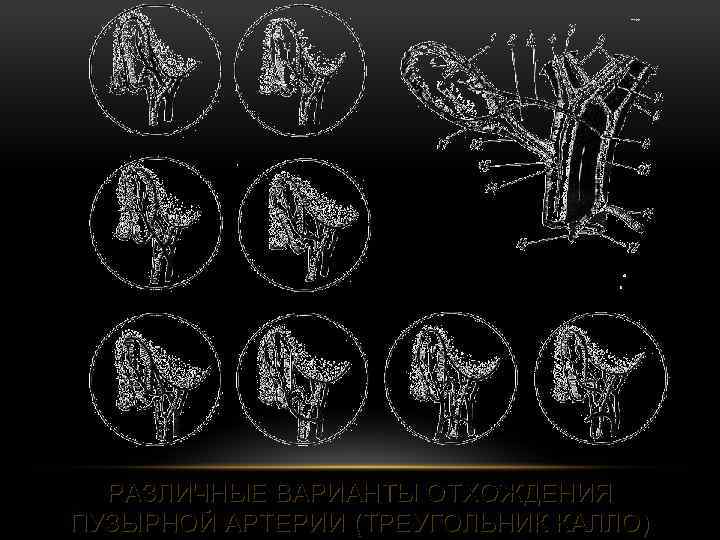

РАЗЛИЧНЫЕ ВАРИАНТЫ ОТХОЖДЕНИЯ ПУЗЫРНОЙ АРТЕРИИ (ТРЕУГОЛЬНИК КАЛЛО)

РАЗЛИЧНЫЕ ВАРИАНТЫ ОТХОЖДЕНИЯ ПУЗЫРНОЙ АРТЕРИИ (ТРЕУГОЛЬНИК КАЛЛО)